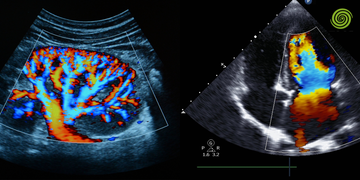

La integración de Doppler de alta sensibilidad (Power Doppler o Doppler de flujo lento) permite identificar la angiogénesis tumoral. Sin embargo, en la práctica clínica, la presencia de flujo no es sinónimo de malignidad, sino un indicador de actividad metabólica. El reto está en diferenciar los vasos de resistencia normal de aquellos con flujos de alta impedancia o patrones tortuosos que sugieren procesos neoplásicos. Esta distinción es lo que separa un informe mediocre de una interpretación con alto valor predictivo positivo.

Doppler Color y Power Doppler: Son esenciales para mapear la arquitectura vascular. En lesiones sospechosas, buscamos vasos nutricios periféricos que penetran radialmente en la lesión. Un error común es saturar la ganancia buscando flujo, lo que genera artefactos que ocultan la verdadera morfología del vaso.

Doppler Pulsado (Espectral): Aquí es donde el clínico mide índices de resistencia (IR) y de pulsatilidad (IP). Aunque no hay un punto de corte universal para malignidad, un IR elevado suele asociarse a la rigidez de los vasos tumorales.

3. ¿Qué diferencia técnica existe entre el Doppler Color y el Power Doppler en mama?

El Doppler Color codifica la dirección y velocidad media del flujo, lo cual es útil para identificar vasos principales. El Power Doppler (o Doppler de Energía) se basa en la amplitud de la señal, lo que lo hace mucho más sensible para detectar flujos lentos y vasos pequeños (microvasculatura), independientemente del ángulo de insonación. Para la caracterización de nódulos sospechosos, el Power Doppler es técnicamente superior por su mayor sensibilidad.